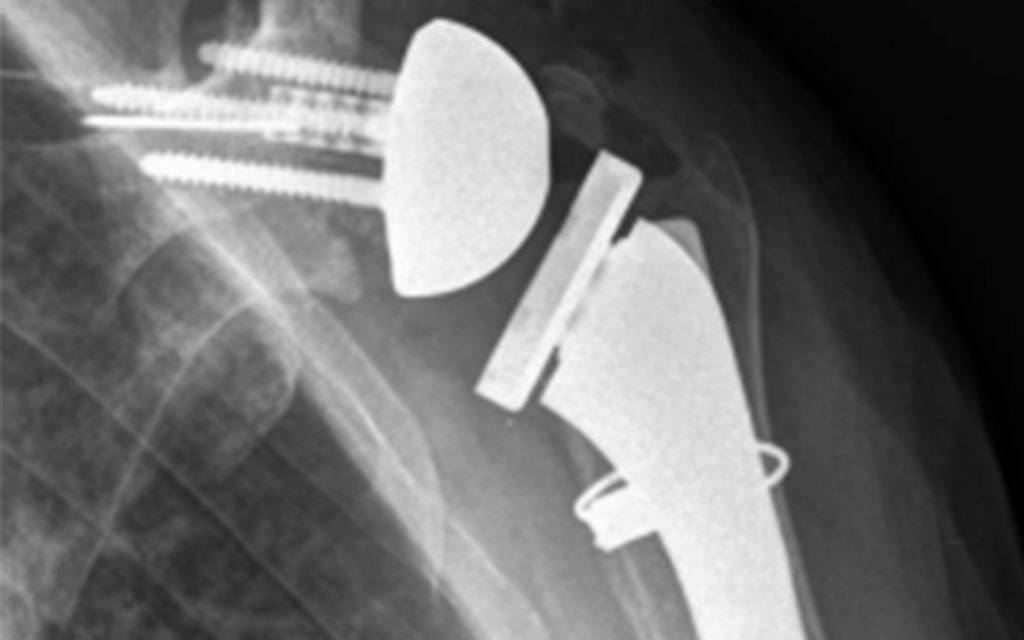

One example is a 79-year-old male with symptomatic cuff tear arthropathy on the right and a failed total shoulder arthroplasty (TSA) on the left due to rotator cuff insufficiency. Because of the predictable nature of performing an rTSA as a primary, the right side was addressed first. At three months post-op he had IR to L5.

At four months post-op, he elected to have a revision of the failed TSA on the left. This required explanation of the stem—because the stem was not a platform stem—and allograft structural bone graft to the glenoid defect after removal of the prosthetic glenoid. At six months follow-up, he had IR to S1 on the revision side.